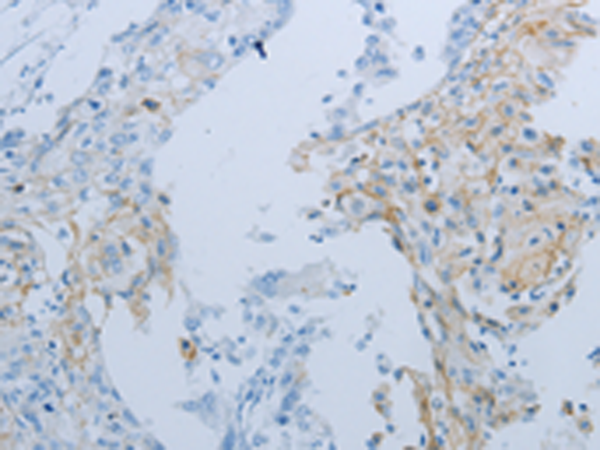

分类: 科研抗体货号: P10717别名: ATG6; VPS30; beclin1应用: WB,IHC反应种属: Human, Mouse, Rat